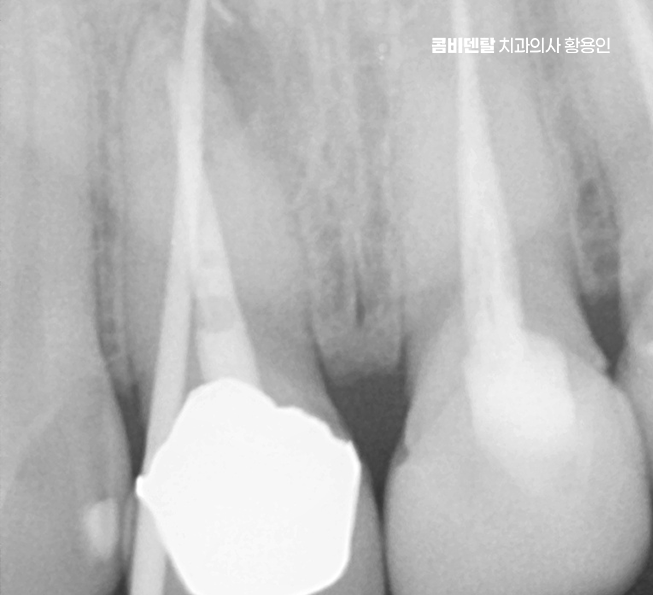

문제가 심해지면 결국 신경에까지 세균이 도달해서 통증이 생기고 찬물에 시리거나, 저리듯이 쑤시는 느낌, 잇몸에 작은 뾰루지가 생기는 경우도 있으며 그냥 손가락으로 눌렀을 때 묵직한 압통이 있다면 이미 신경치료가 필요한 상태일 가능성이 높아지고 이런 경우엔 기존 보철물을 제거하고, 내부 충치 상태를 확인한 뒤, 신경치료부터 들어가야 할 수 있었어요

신경치료는 치아 내부의 염증이나 감염된 신경을 제거하고, 뿌리 속을 소독해서 밀봉하는 치료로 앞니는 뿌리가 하나인 경우가 대부분이라 어금니보단 비교적 간단하지만, 이미 보철을 한 치아는 구조적으로 약해져 있기 때문에 세심한 처치가 필요한데 뿌리 일부가 약해져 있거나 균열이 생겨 있을 가능성도 있어서 이런 경우엔 정밀한 신경치료가 필요하며 감염이 심한 경우엔 2~3회에 걸쳐 치료가 이뤄지고, 상태가 안정된 뒤에 마무리되는 거예요.

결국 앞니 치료는 치료 후 관리도 잘 고려해야 하는데 신경치료한 치아는 감각이 줄어들기 때문에 문제가 생겨도 통증이 없는 경우가 많아서 정기적으로 엑스레이를 찍고 뿌리 상태를 확인하는 게 필요하고 잇몸 관리를 위한 스케일링도 꼭 주기적으로 받아야 한다는 점도 잊지 마시길 바라고 있었어요